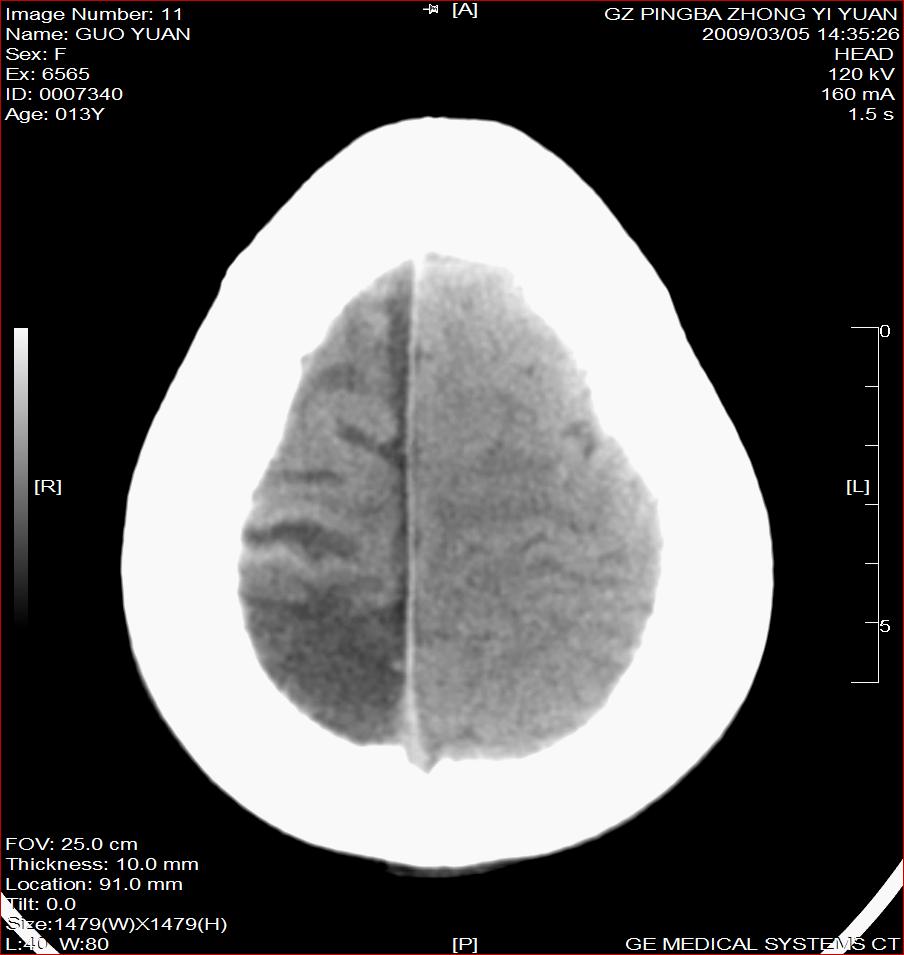

以下是引用杀毒软件在2009-3-6 17:32:00的发言:[br]右侧额颞顶部脑沟裂增宽,颞顶部楔形稍低密度影,侧脑室体部明显增宽,余脑实质内未见异常,中线结构居中。[br][br]考虑---右侧大脑半球发育不良并脑沟裂发育畸型可能性大

以下是引用随光逐影在2009-3-6 18:35:00的发言:[br]1)考虑右侧幕上半球发育不良并脑软化灶。2)双侧额部头皮软组织肿胀。